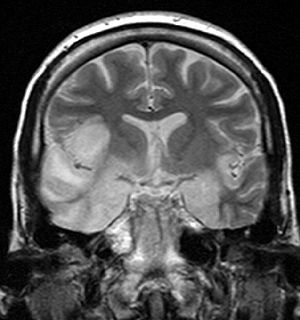

2. A fall with subsequent neurology: A 70 year old lady falls, hits her head and presents to A&E. On admission her chest x-ray looked normal. Initial CT of her head was normal. Then she becomes acutely short of breath and has a CT scan. This shows lots of blood in her chest (left side) – this is called a haemothorax. She has a chest drain inserted to help her breathing. The next day she is quite confused. ? Delirium (acute confusion related to painkillers/infection/trauma of admission). This was very out of character for her so a CT head was performed again. This looked relatively normal, however the brain looked large for someone in their 70’s (the brain shrinks with age), but was reported as normal (there was certainly no obvious abnormality). She then deteriorated and dropped her conscious level and had to be intubated. What is going on here? An LP was performed with white cell count of 1 and a protein level of 1.09. Neuroradiologists agreed that the CT scan looked normal. Then the PCR from the LP showed HSV type 1. MRI then confirmed this in the temporal lobes. This is a very dangerous condition that needs prompt and sometimes prolonged treatment with antiviral therapy.

Diagnosis: HSV Encephalitis Type 1